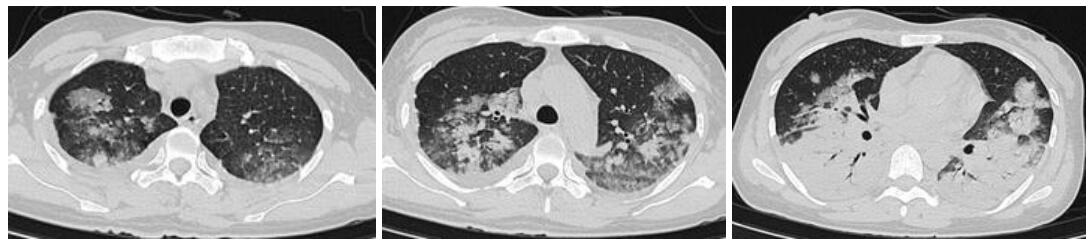

入院查体:体温39 ℃,脉搏87次/min,呼吸30次/min,血压111/75 mmHg(1 mmHg=0.133 kPa);神清,无皮疹,浅表淋巴结无肿大,双肺闻及少许干湿啰音,心律齐,未闻及杂音,腹软,肝脾肋下未触及;胸部CT示两肺感染,见图 1;甲、乙型流感病毒抗原检测阴性。入院诊断:重症社区获得性肺炎。予无创机械通气,莫西沙星抗感染,帕拉米韦抗病毒治疗,效果欠佳,遂转入ICU。入ICU血气:FiO2 70%,pH 7.44,PCO2 30.5 mmHg,PO2 88.2 mmHg,Lac 0.9 mmol/L,PO2/FiO2 126.0,考虑合并急性呼吸窘迫综合征,予气管插管机械通气,右美托美定+丙泊酚镇静、哌拉西林他唑巴坦、奥司他韦、甲泼尼松龙等治疗。复查胸部CT示:两下肺实变。行俯卧位通气,行肺泡灌洗液mNGS检测:鹦鹉热衣原体(序列数773),未检测到病毒及其他细菌,改用多西环素+莫西沙星抗感染。治疗效果好,1周后复查肺CT示病灶吸收明显,见图 2;第10天脱机拔管,转出ICU。

| 两肺斑片状密度增高影,边界模糊,两下肺大片实变影 图 1 病例1入院时胸部CT结果 |

| 两肺片状模糊影,双肺下叶实变渗出病灶较前明显吸收 图 2 病例1入院1周胸部CT结果 |